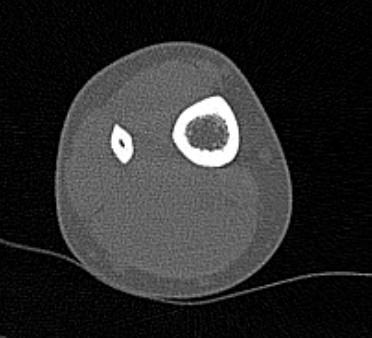

Мультиспиральная компьютерная томография – это современный высокоинформативный рентгенологический метод диагностики различной патологии костно-суставного аппарата, который позволяет выявлять патологические изменения голеностопного сустава на ранней стадии.

Во время исследования рентгеновская трубка томографа вращается вокруг исследуемой области и производит множество послойных снимков с шагом от 0,5 мм. Полученные снимки поперечного сечения с помощью компьютерной программы могут быть преобразованы в 3D-изображения исследуемого органа. Это позволяет выявлять различные патологические процессы на начальных стадиях и назначать своевременное лечение.

За счет быстроты, доступности и неинвазивности (то есть исследование не требует вмешательства в организм) метод КТ особенно востребован в ортопедии и травматологии. Мультиспиральная КТ лучше всего визуализирует плотные ткани, такие как кости и хрящи. Поэтому, в первую очередь, применяется для диагностики травм суставов (вывихов, подвывихов, переломов).

В отличие от обычного рентгена, при котором изображения костных структур накладываются друг на друга, что затрудняет диагностику, компьютерная томография дает возможность увидеть объемную модель сустава, наглядно оценить пространственное соотношение внутрисуставных структур, суставных поверхностей, расположение костных отломков при переломах и травмах. Это особенно важно в ходе подготовки к оперативному вмешательству и в послеоперационном периоде для оценки успешности проведенной операции.

При необходимости визуализации мягких тканей сустава, например, при подозрении на опухолевый процесс, дополнительно проводится КТ с внутривенным болюсным контрастированием. В этом случае для лучшей визуализации патологического очага пациенту внутривенно вводится йодсодержащий контрастный препарат. Контрастное вещество накапливается в патологических участках и обеспечивает их яркую визуализацию на фоне неизмененной ткани. С помощью контрастирования можно визуализировать кровеносные сосуды, выявить первичные опухоли и метастазы в области голеностопного сустава, обнаружить воспалительные и дегенеративные изменения.